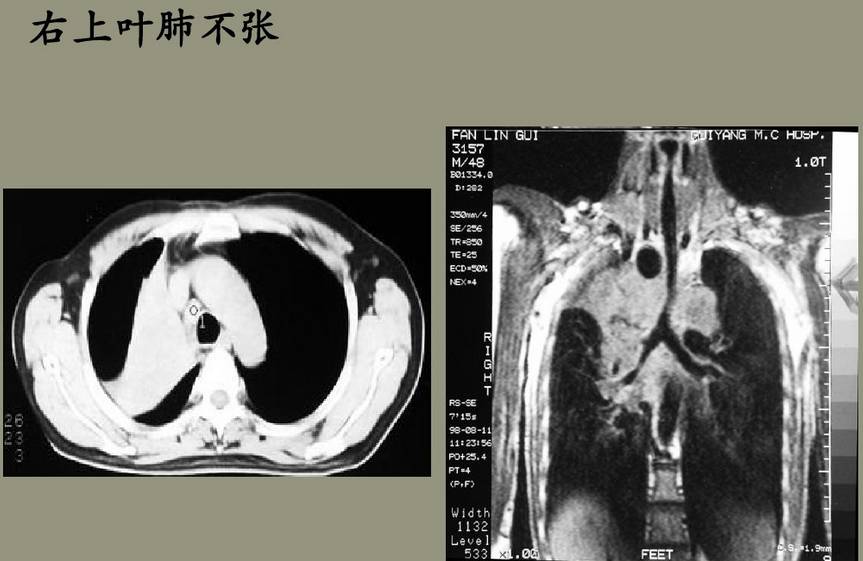

肺叶不张和肺段不张各有何X线表现?(1)右肺上叶不张:横裂上移呈折扇形或三角形致密阴影,尖端指向肺门,甚至全部位于上纵隔旁。(2)右肺中叶不张:右心缘旁致密阴影,上缘不超过肺门。直立的正位片上常显影不清。侧位片显示较为清楚,呈三角形、梭形或线形,尖端指向肺门。